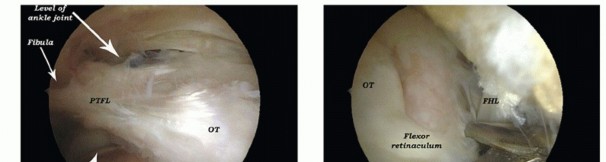

Removal of a symptomatic os trigonum (TECH FIG 5), a nonunited fracture of the posterior talar process, or a symptomatic large posterior talar prominence requires partial detachment of the posterior talofibular ligament and release of the flexor retinaculum, both of which attach to the posterior talar prominence.

TECH FIG 5 • Endoscopic procedure for removing an os trigonum and releasing the FHL in a left ankle. A. Os trigonum (OT) with its connection to the posterior talofibular ligament (PTFL), flexor retinaculum, and talocalcaneal ligament (TCL). B. Cutting through the flexor retinaculum. C. Cutting through the TCL. D. Releasing the PTFL. E. Overview of the os trigonum released from its related anatomic structures. F. Postoperative overview. IML , intermalleolar ligament. -

Release of the Flexor Hallucis Longus Tendon

Release of the FHL tendon involves detachment of the flexor retinaculum from the posterior talar process by means of a punch (TECH FIG 6).

22 TECH FIG 6 • Endoscopic procedure for releasing of the FHL tendon (B) involves detachment of the flexor retinaculum (C) from the posterior talar process (A) by means of a punch. D , talus; E , subtalar joint. -